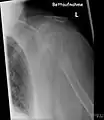

- Vues de fractures pathologiques

Fracture pathologique de l'humérus sur une métastase de carcinome du rein